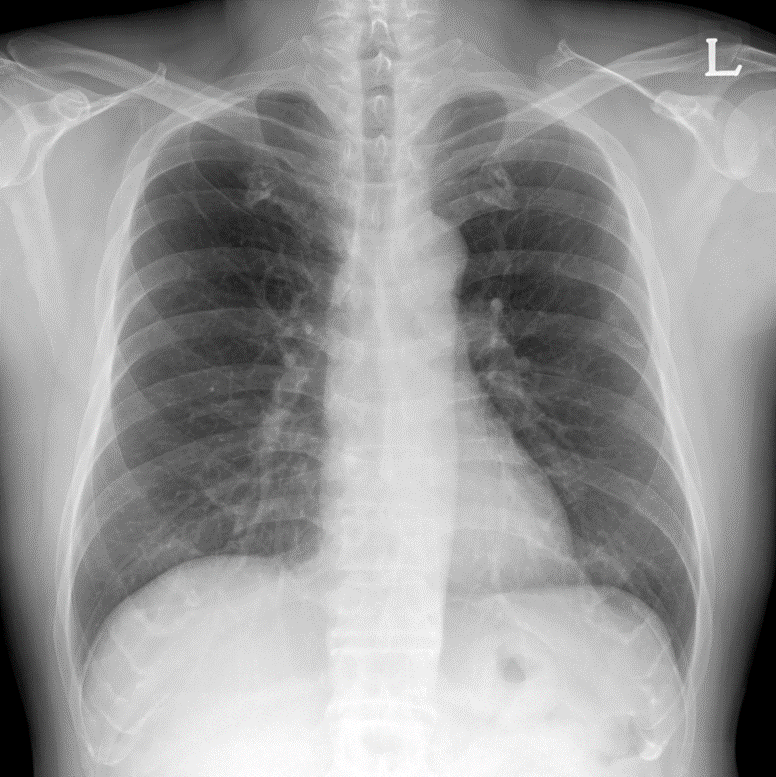

A 58-year-old male with a history of hypertension and dyslipidemia presented with CCS Class III angina persisting for six months. His past medical history was significant for percutaneous coronary intervention (PCI) performed nine years prior, involving a distal right coronary artery (RCA) lesion and a left anterior descending (LAD) chronic total occlusion (CTO). Current medications included aspirin, carvedilol, nicorandil, and statins. Physical examination and vital signs were unremarkable.

Relevant Test Results Prior to Catheterization

Echocardiography demonstrated a normal left ventricular ejection fraction but revealed akinesia of the basal septum and inferior wall. Myocardial SPECT showed a large, reversible perfusion defect in the inferior wall with an ischemia extent of 4%. Pre-procedural CT angiography identified a complex RCA CTO characterized by a severe calcified nodule at the proximal segment, predicting high difficulty for device crossing.